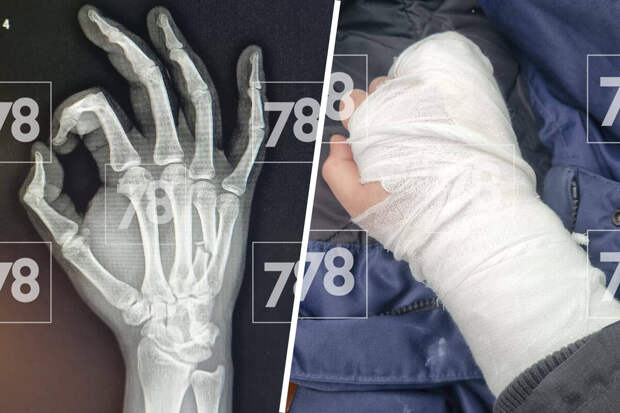

Медик выписал пациента домой, но тот через некоторое время вернулся с металлической лопатой для снега и несколько раз ударил врача. По словам потерпевшего, агрессор в момент нападения был пьян.Врачу диагностировали закрытую черепно-мозговую травму и закрытый перелом правой кисти.